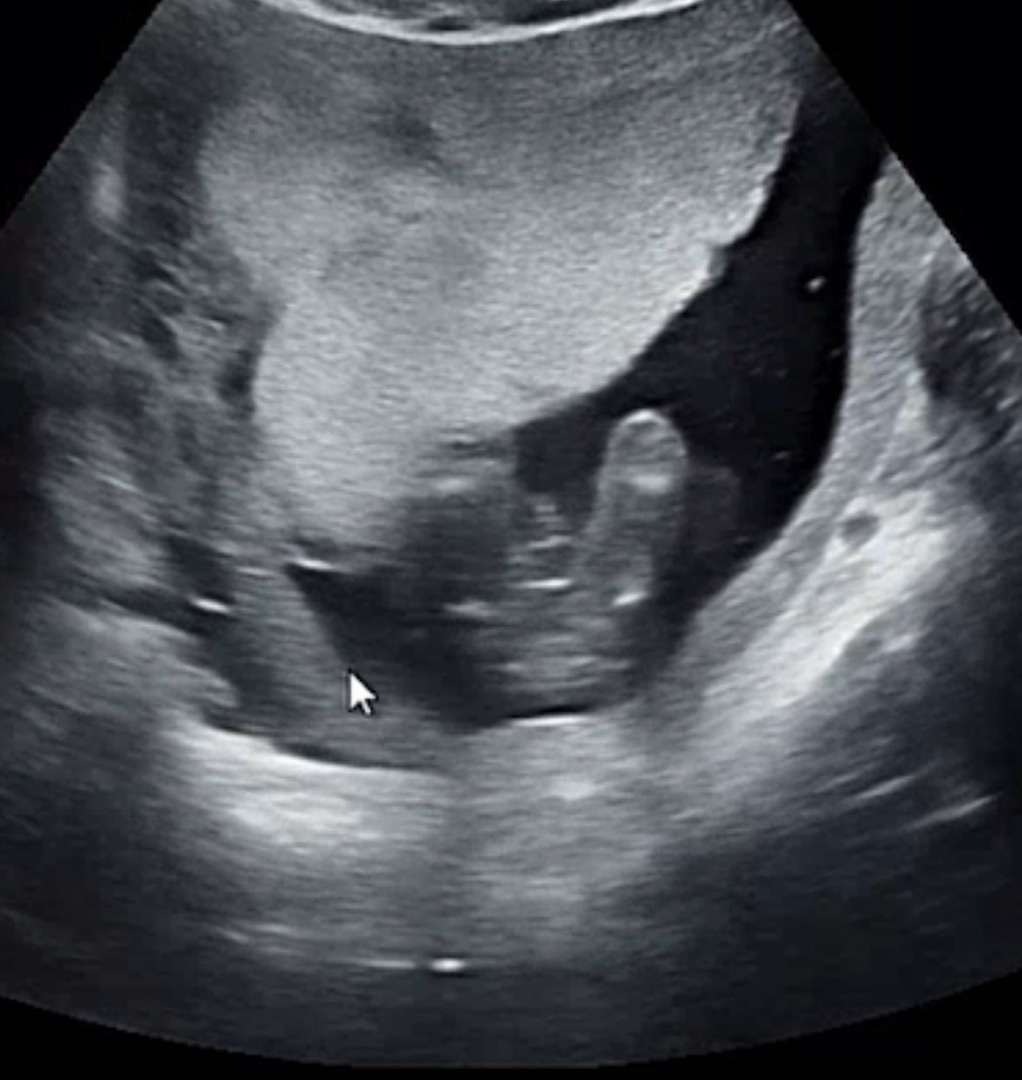

어제 16주 2차가형아검사했는데 성별이 뭘까요,,?!

어제 16주 2차기형아검사를 위해 병원 갔는데 초음파상으로 애기가 잘 안보여줘서 확정을 안해주시드라구여,,,, 이날만 기다렸는데,,, 의사쌤 말로는 딸같지만 확정은 아니라고 하시는데 한달 후 정밀초음파검사를봐야알수있더고하더군요,,,;; 맘님들은 어떻게보시나요~?!

아기 다리가 너무 아래쪽에있다고 잘안보인다고만말씀하시드라구요,, 다른 분들은 16주에 대부분 보시든데,,, 담주나되어서 동네병원에 가보려구요,,,